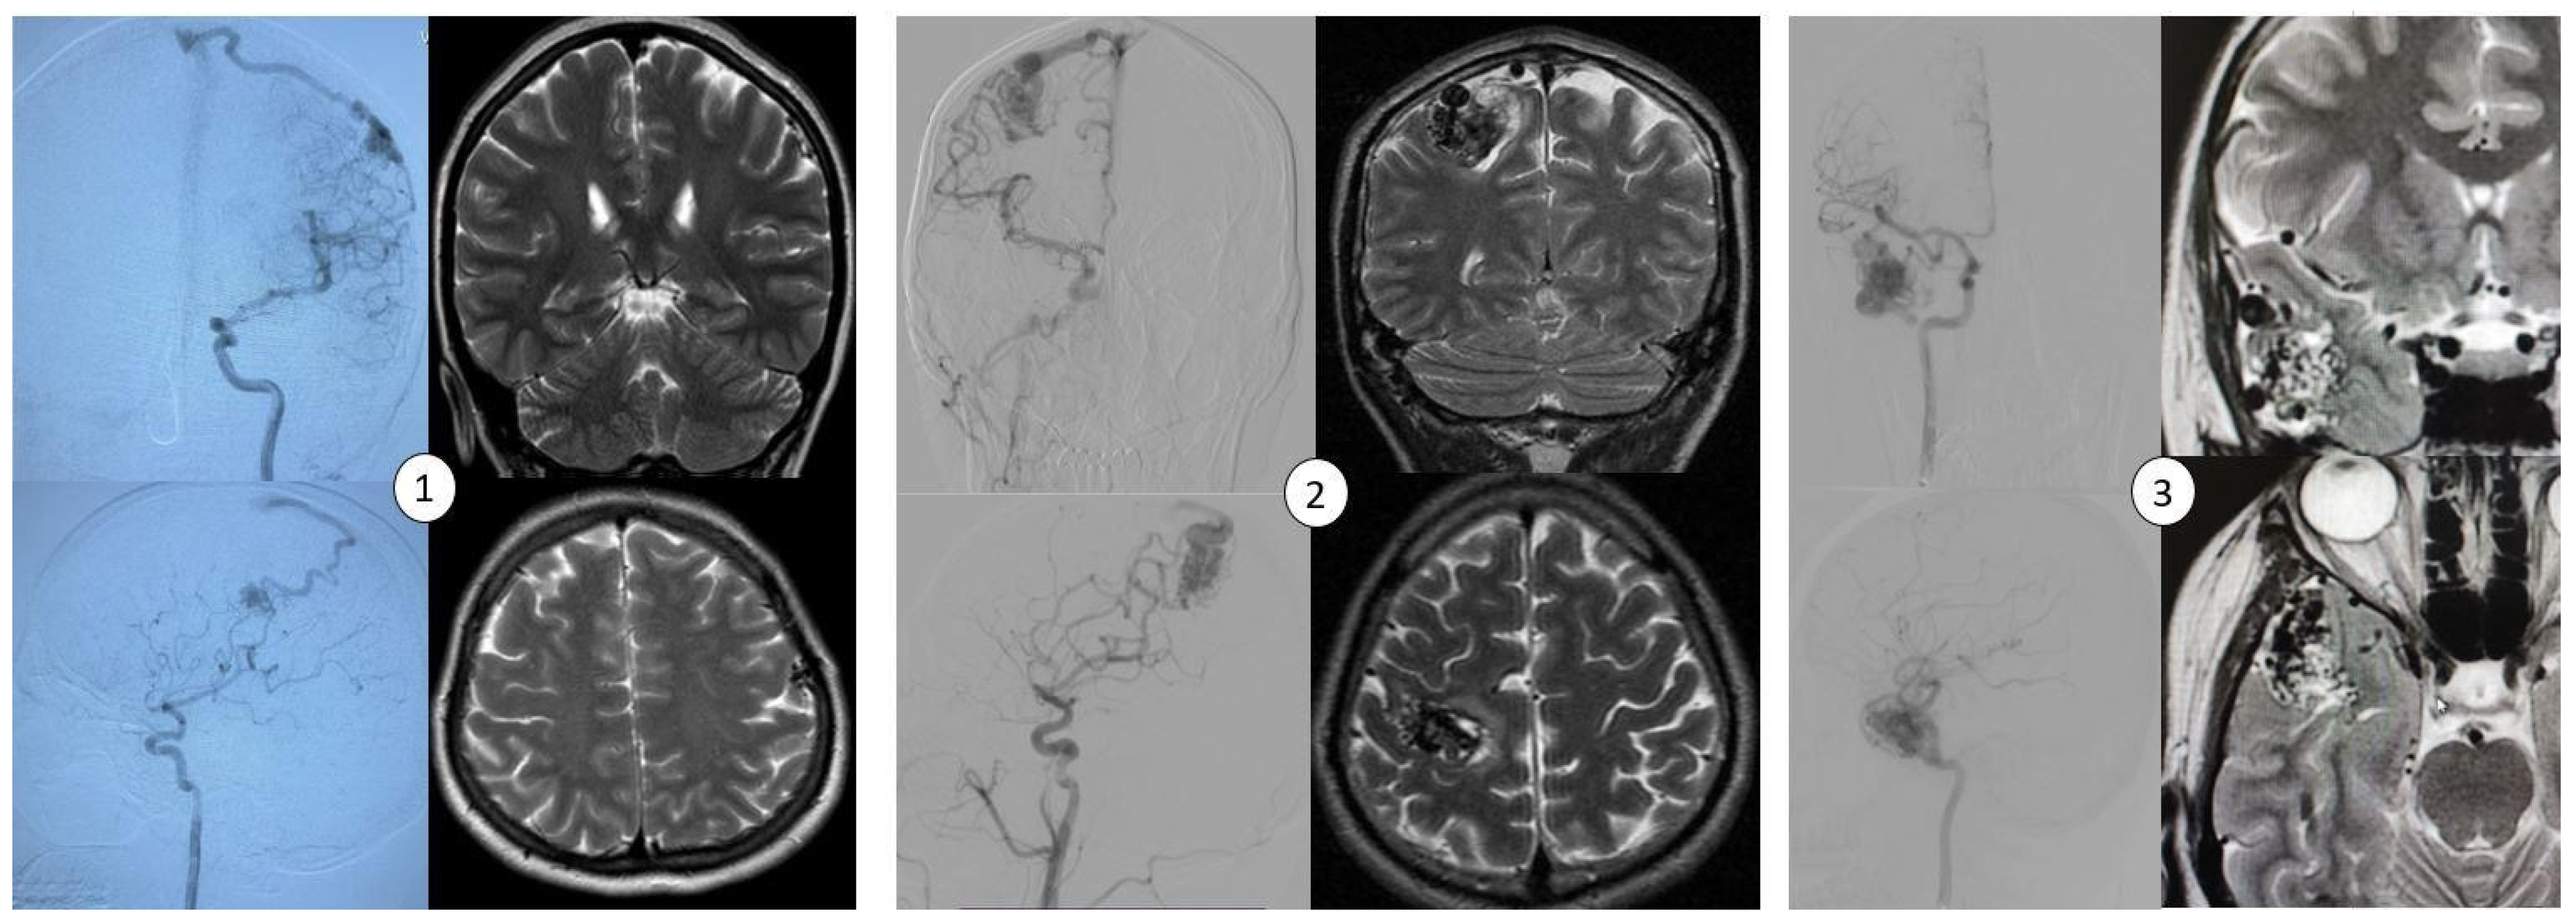

This study was conducted in a cohort of three patients (AVM1–3) who underwent microsurgical resection of bAVMs at the National Centre for Neurosurgery (NCN) in Astana, Kazakhstan. bAVMs were diagnosed using magnetic resonance imaging (MRI) and digital subtraction angiography (DSA) performed using a biplane system (Artis Zee Biplane System, Siemens, Erlangen, Germany) (Figure 1). Diagnostic imaging was reviewed by a multidisciplinary team of neuroradiologists and neurosurgeons. The diagnoses were confirmed through histopathological analysis of resected specimens.

Figure 1.

Neuroradiological imaging findings of bAVM lesions, including cerebral angiograms in both anterior and lateral projections and MRI scans (T2-weighted sequences) in the axial and coronal planes. The images correspond to the three patients described in the study: (1) AVM1—located in the left frontal lobe, (2) AVM2—located in the right parietal lobe, and (3) AVM3—located in the right temporal lobe.